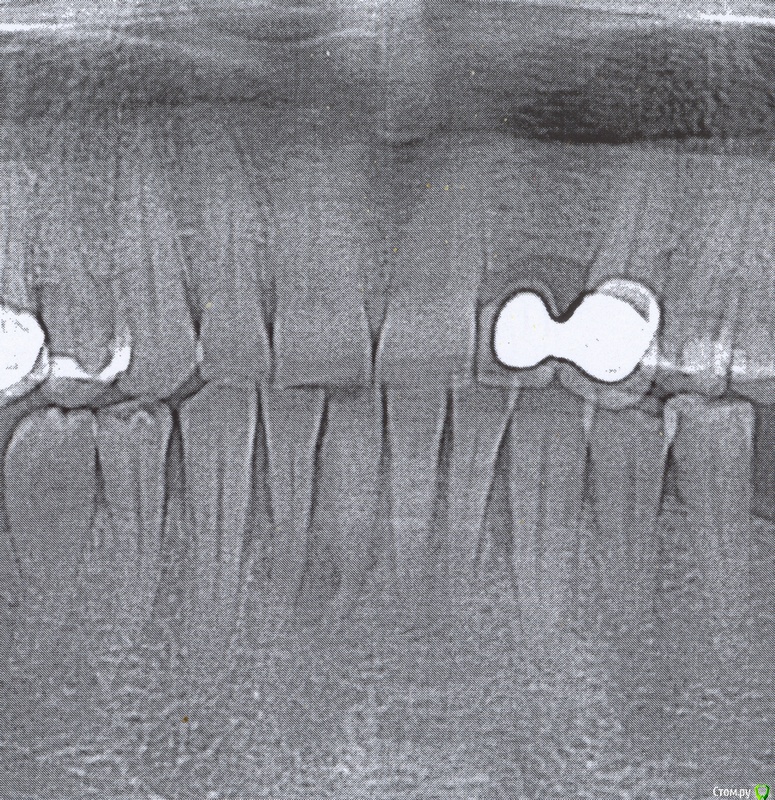

Violin Опубликовано 10 декабря, 2015 Автор Поделиться Опубликовано 10 декабря, 2015 Ну вот ещё пара снимковОдин с КТ(другой разрез) , второй панорамный... Ссылка на комментарий

Violin Опубликовано 11 декабря, 2015 Автор Поделиться Опубликовано 11 декабря, 2015 Такие тоже не пойдут, да? Ссылка на комментарий

red_butler Опубликовано 11 декабря, 2015 Поделиться Опубликовано 11 декабря, 2015 Такие тоже не пойдут, да? похоже как минимум один зуб, все таки придется удалять. Ссылка на комментарий